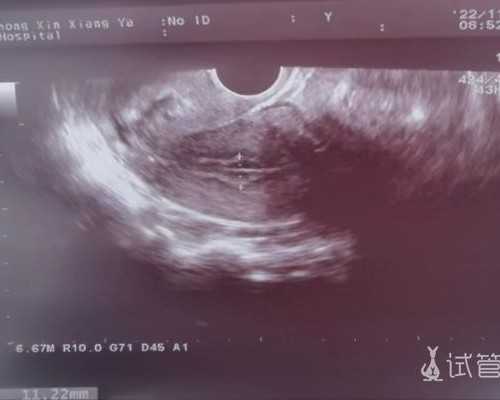

植入后9天抽血测Hcg,两百多,着床啦,再一周后抽血看hcg翻倍,一万多啦,再一周后阴超看胎心,弱弱的扑通扑通声。